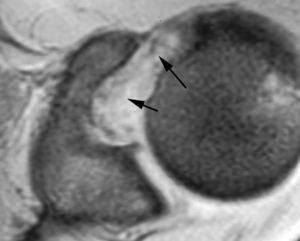

Lesión de Perthes

La lesión de Perthes es similar a la de Bankart, con la excepción de que no existe rotura capsuloperióstica, aunque el periostio puede estar separado del borde anterior del margen glenoideo (fig. 10). Esta lesión puede ser difícil de visualizar, incluso con artrorresonancia, a menos que se obtengan imágenes con la posición de abducción y rotación externa (ABER). En un estudio de 10 casos, verificados quirúrgicamente, Wisher et al17 comprobaron que el 50% de las lesiones de Perthes sólo podían visualizarse en la posición de ABER.

Fig. 10.--Lesión de Perthes. Artrorresonancia T1 con saturación grasa en posición ABER (abducción y rotación externa), donde se observa un arrancamiento parcial del labio glenoideo (flecha) con conservación de la unión capsuloperióstica.